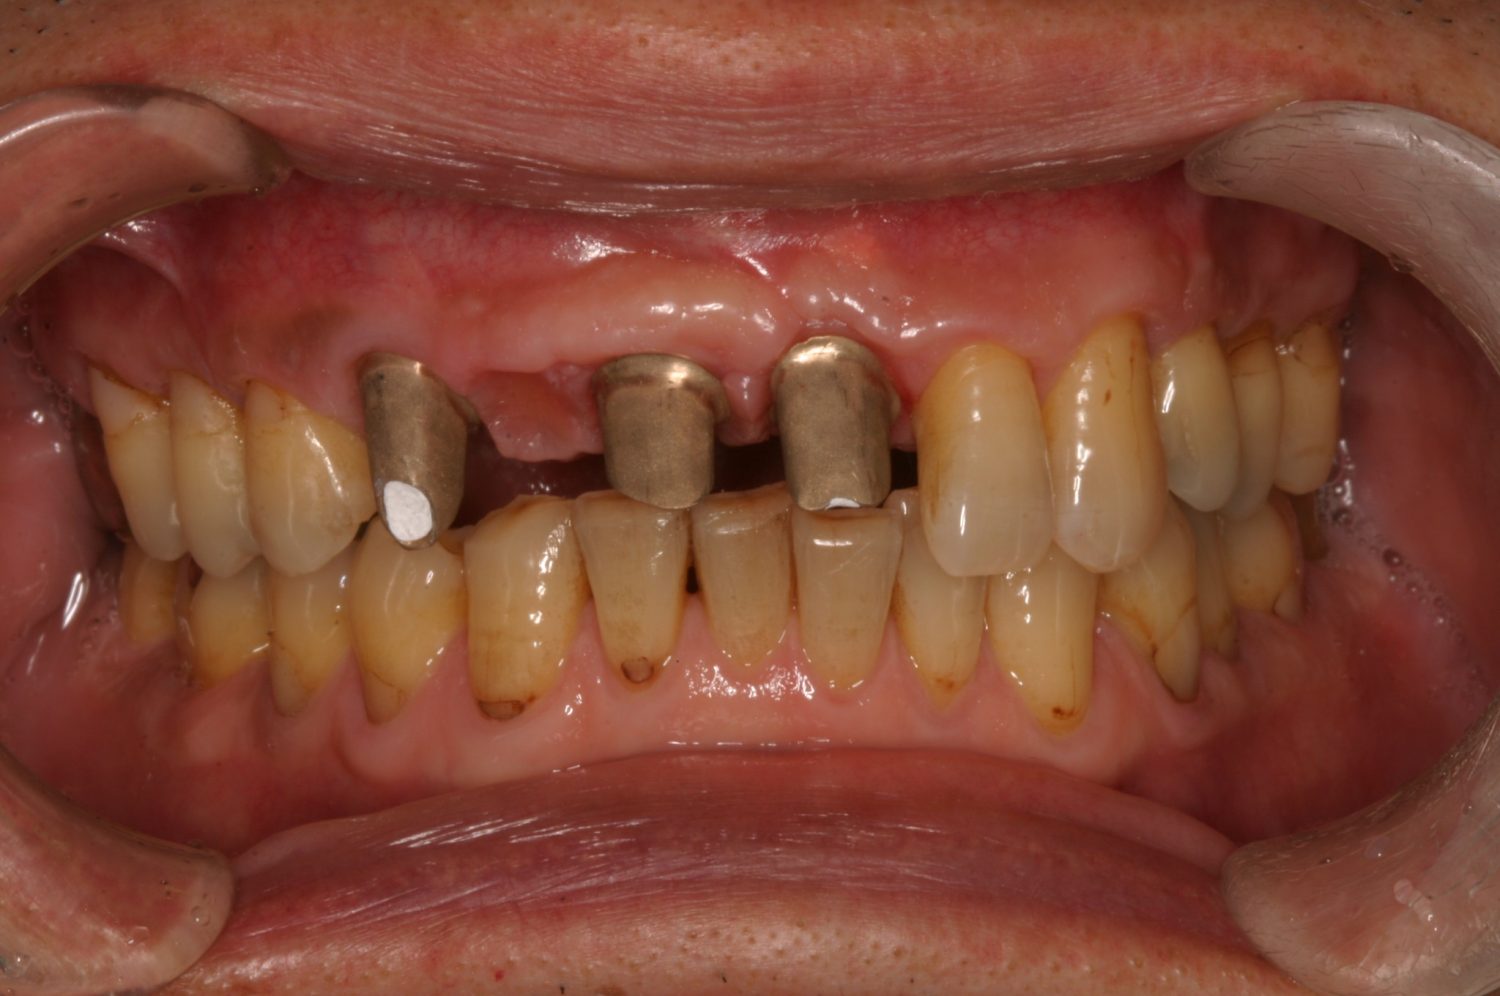

Before

After

修復物の脱落時に支台築造のポスト部で歯質を破折。抜歯即時インプラント埋入をおこなったケース。

残存した歯根に感染が少なく、抜歯時即時にインプラント埋入手術を行った。術後〇年経過し安定している状態。